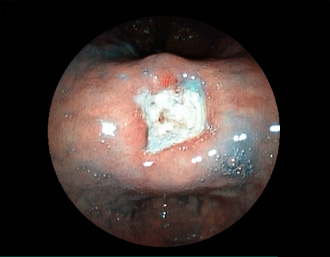

症例1:胃潰瘍(37才、男性)

①胃潰瘍(Stage A1)

健診:胃レントゲン検査で、胃角部ニッシェを指摘され当院受診。

胃角部小弯に、深くて大きな、大きさ約10mmの胃潰瘍(stage 1)があり、潰瘍底は一部白苔はみ出しを認める。エソメプラゾールマグネシウム水和物投薬で治療開始しました。